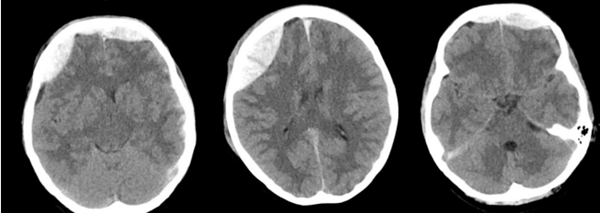

近日,中山大学附属第一医院(简称小妲己直播app )广西医院神经外科团队成功救治一名因外伤导致迟发性硬膜外血肿的患者,经开颅硬膜外血肿清除术后,患者最终康复出院,并为科室送来一面写有“医术精湛挽危厄,仁心厚德臻至善”字样的锦旗,表达对科室全体医护人员感谢。患者黄女士(化名)是一名警员。因意外受伤被送到小妲己直播app 急诊科救治。小妲己直播app 立即启动绿色通道,为患者进行全面检查,头颅CT提示,额骨、右顶骨有20...